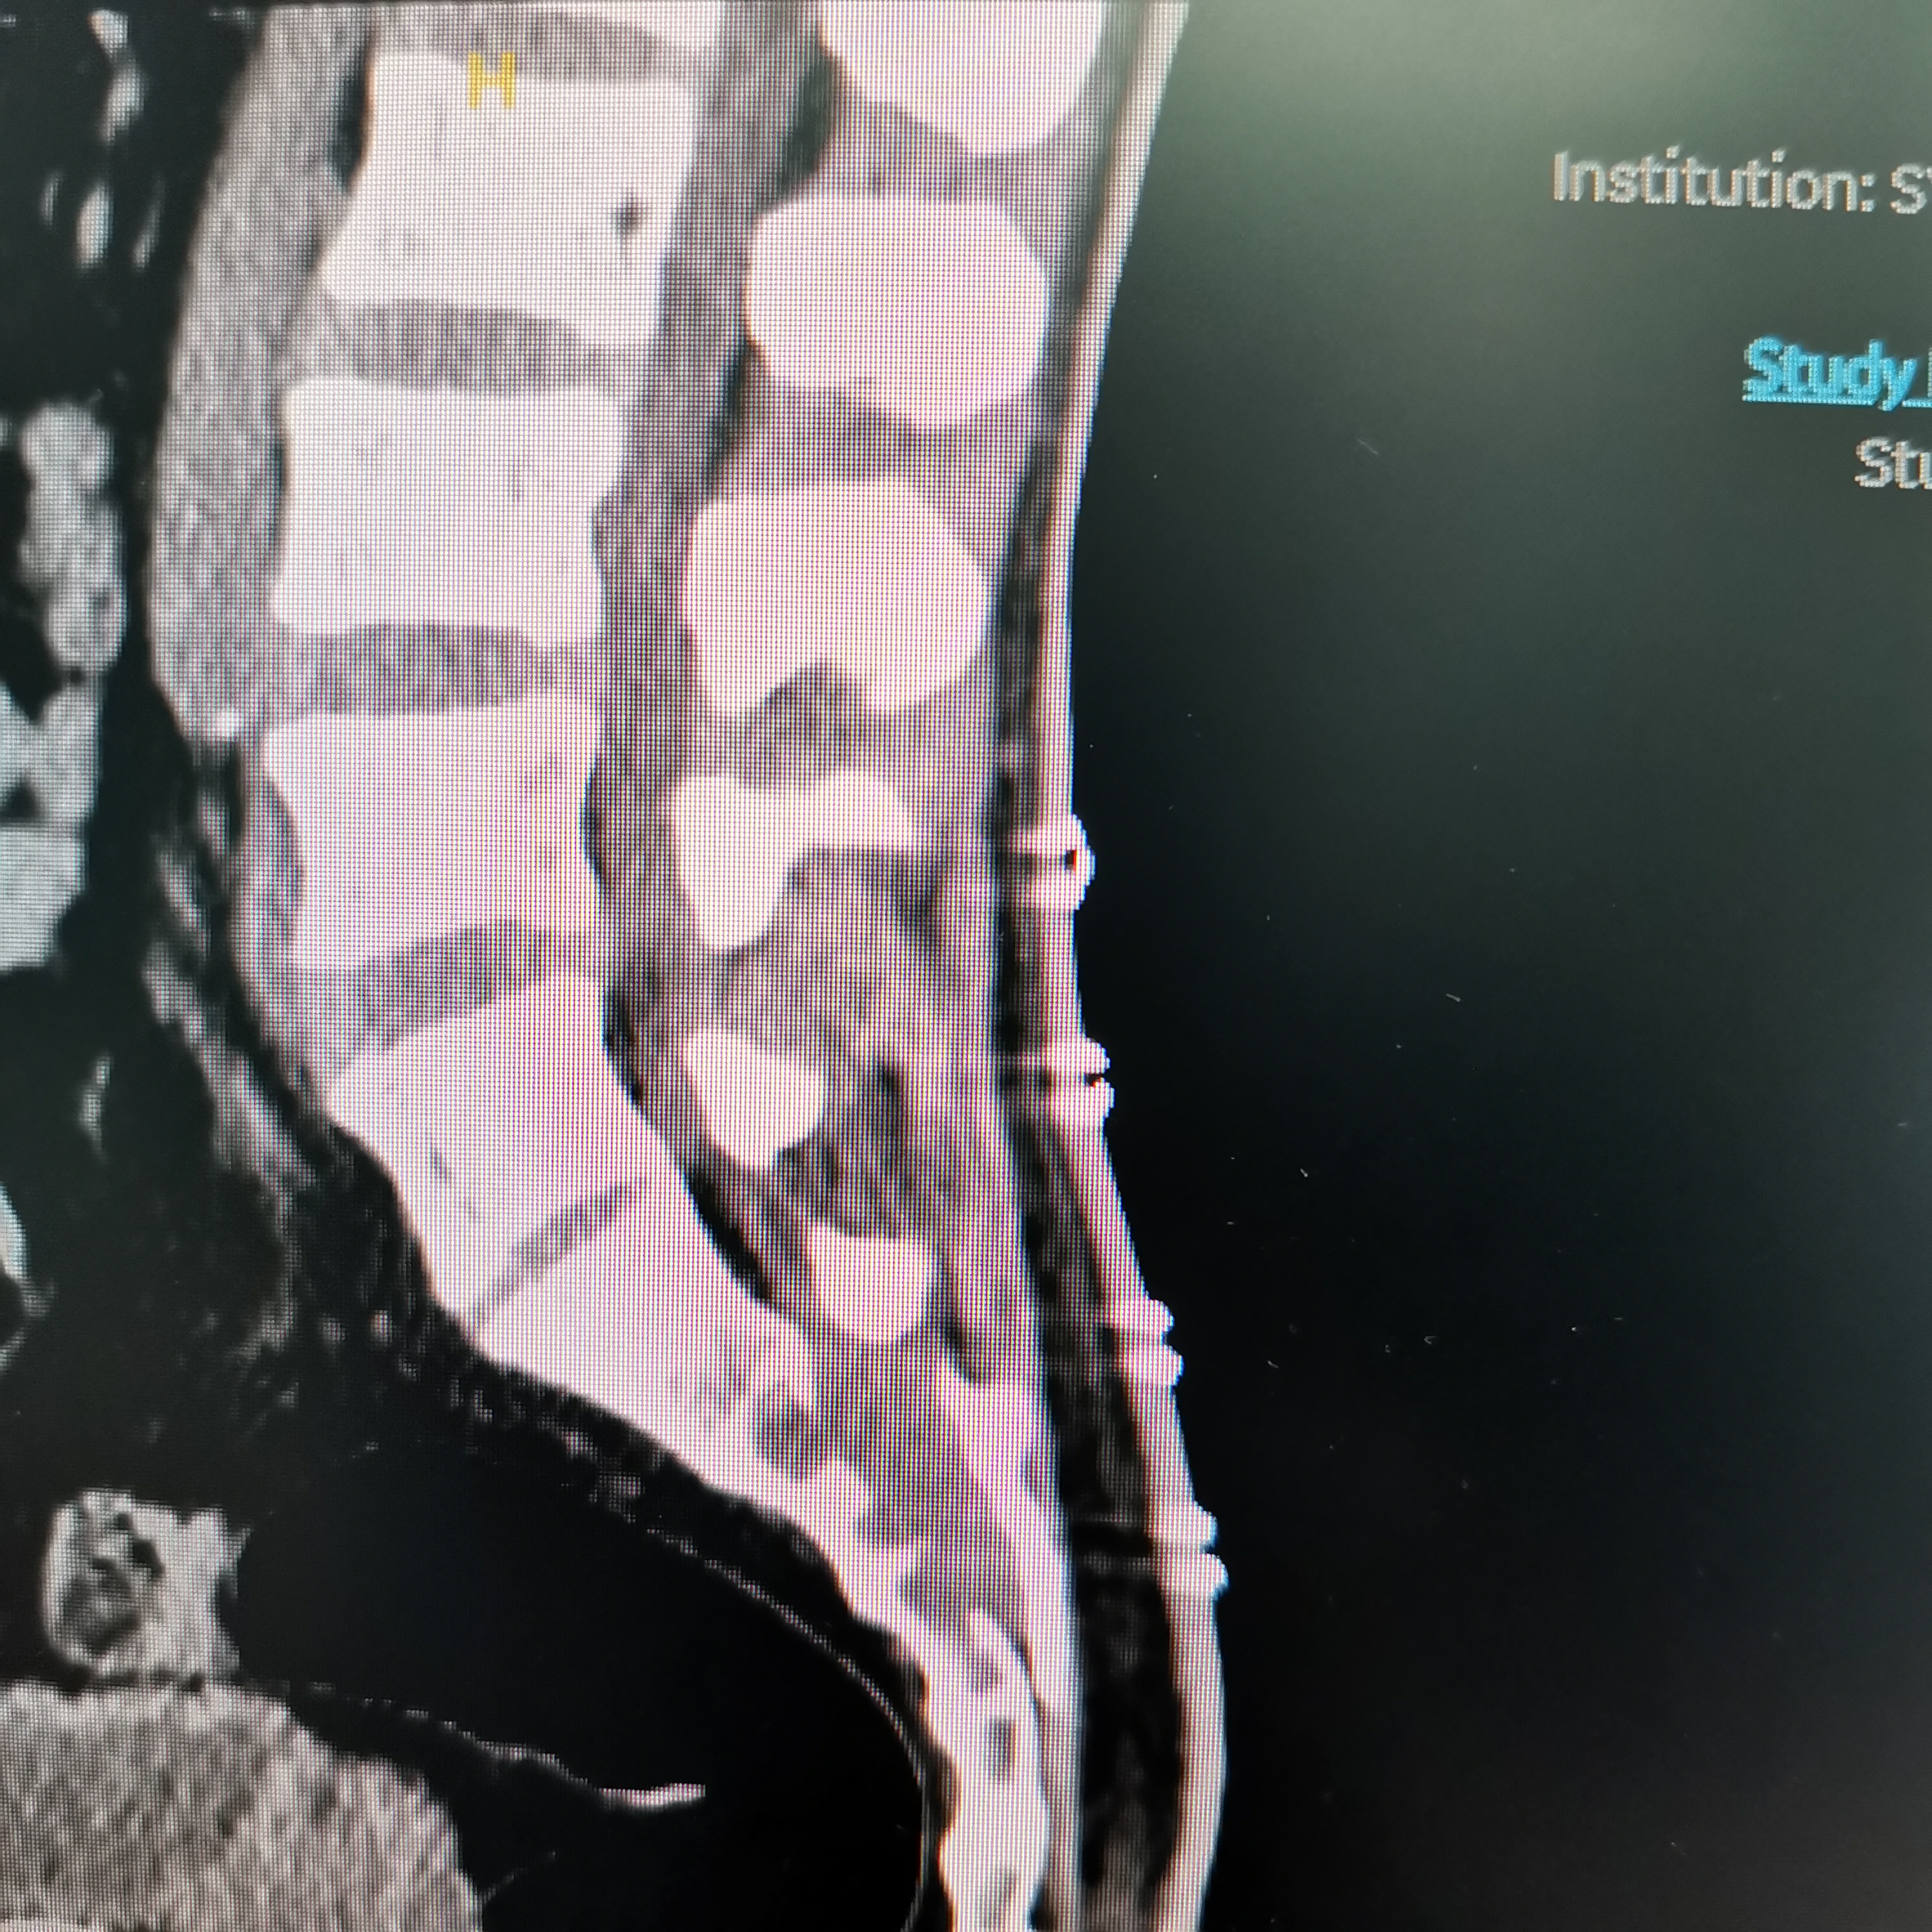

骶椎神经鞘瘤

脊髓脊柱-脊髓脊柱肿瘤